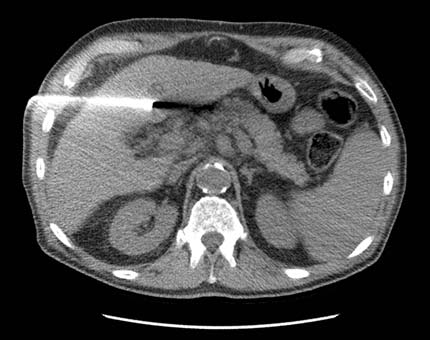

Ablación por radiofrecuencias (RFA) guiada por exploración por TC de un tumor del hígado: Un electrodo múltiple es posicionado en el carcinoma hepatocelular del paciente. Para más información consulte Ablación por radiofrecuencia de tumores hepáticos.

Nota: Las imágenes se muestra para fines ilustrativos. No trate de sacar conclusiones comparando esta imagen con otras en el sitio. Solamente los radiólogos calificados deben interpretar las imágenes.